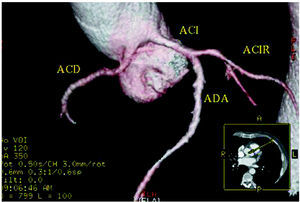

Which technique should we use and in what order? Each medical team should respond to this question in accordance with the available techniques and their experience. What we should do is identify the CAA and its initial course by means of the least invasive technique available to us. Although TEE has been utilized in the diagnosis and identification of the initial course of some CAA, we consider that, given its semi-invasive nature, it should be employed only after other techniques have failed. Today, owing to the increasing availability and the excellent three-dimensional images that can be obtained, it would appear to be prudent to opt for multidetector CT (Figure 5) or for CMRI.49,50 standard coronary arteriography would be indicated if the other tests do not result in a definitive diagnosis. In this respect, the 36th Bethesda Conference51 for the selection of competitive athletes with cardiovascular anomalies published in April 2005 recommended: "Coronary anomalies should be considered in athletes with exertional syncope or symptomatic ventricular arrhythmia and should be investigated using appropriate studies such as echocardiography, CMR or ultrafast computed tomography imaging. Coronary angiography is indicated if other studies are not diagnostic." In brief, they do not opt for 1 diagnostic study or another.

Figure 5. Multislice computed tomography (16 slices); three-dimensional rendered reconstruction showing right coronary artery (ACD) originating in left sinus of Valsalva. ACI indiactes left coronary artery; ACIR, circumflex coronary artery; ADA, anterior descending coronary artery. Courtesy of Dr. Joaquín Alonso, Servicio de Cardiología y Servicio de Diagnóstico por Imagen, Hospital de Fuenlabrada, Madrid, Spain.